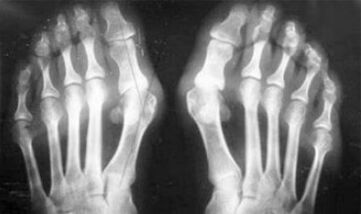

The difference between arthritis and arthrosis of the fingers and hands of the hands is that the first disease is healed and the second is not.Arthritis touches the synovial sheath and the capsule of the joint.

The damage to the cartilage and bone tissue occurs only in the late stages in neglected state.Cartilage tissue is first affected by arthrosis, and then the bones, the inflammation of the synovial membrane is of secondary origin, that is, it develops of their origin.